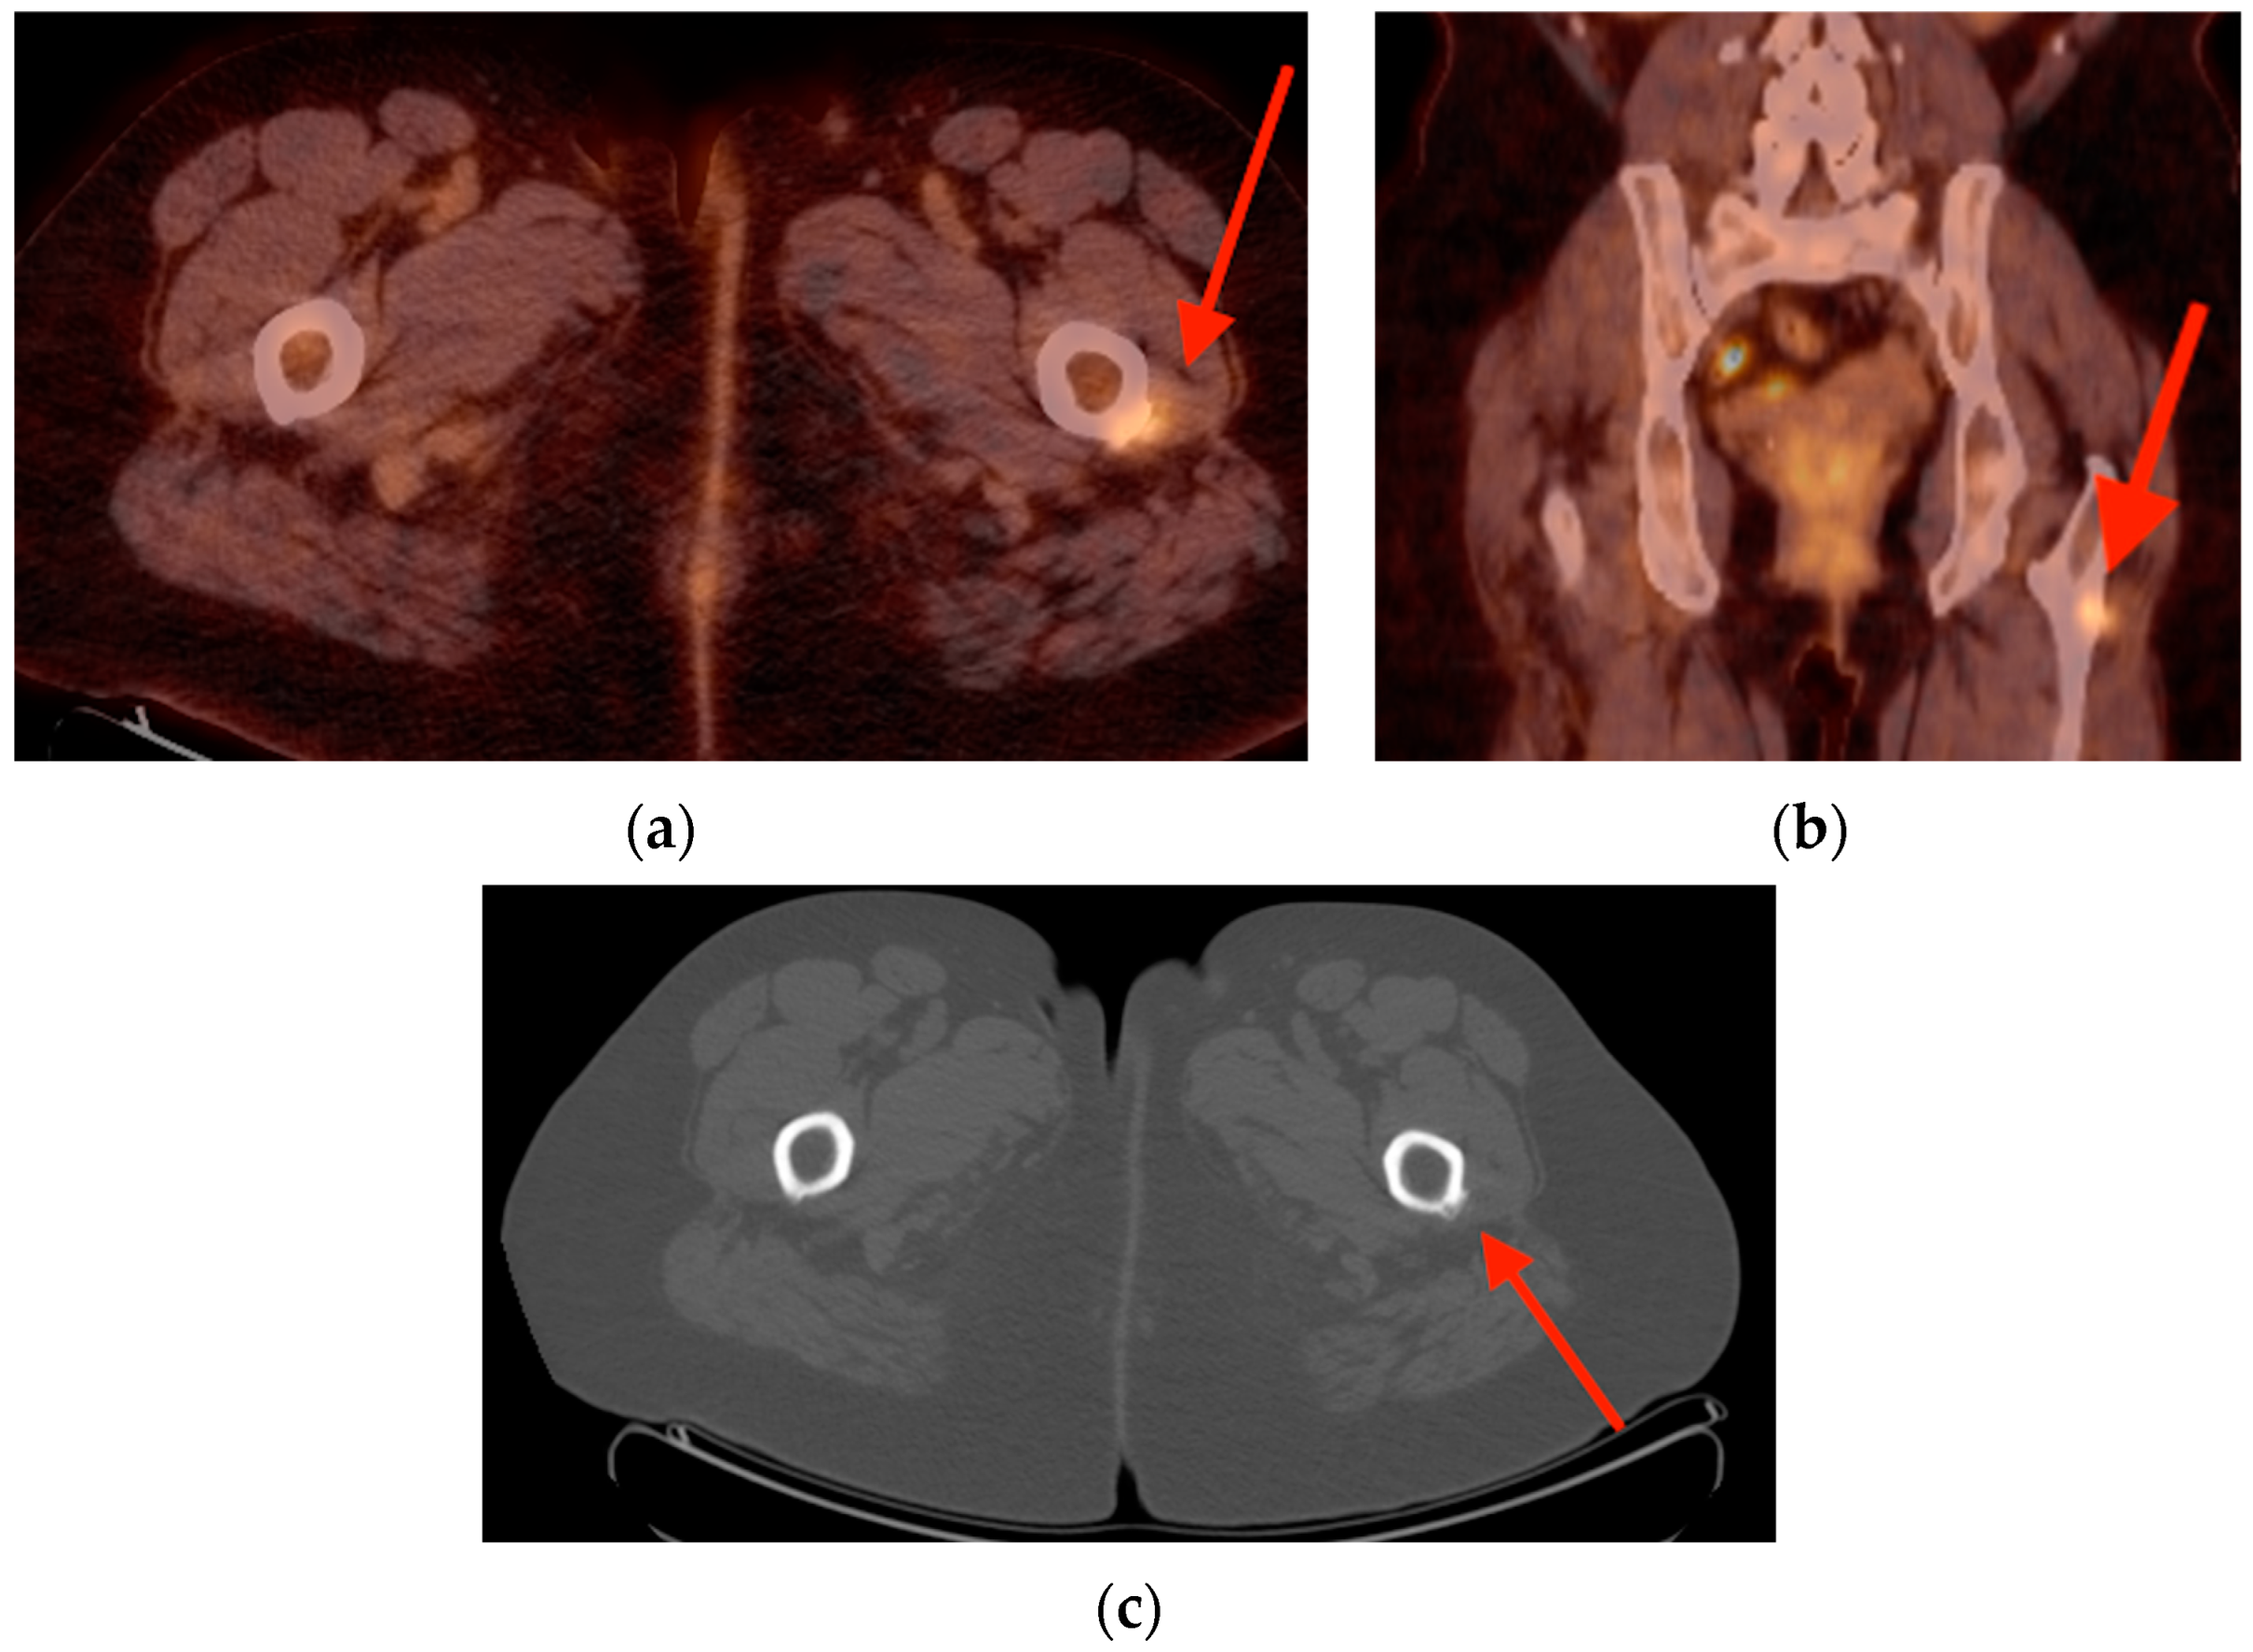

4.1. Tenosynovial Giant Cell Tumor/Pigmented Villonodular Synovitis

- Broski, S.M.; Murdoch, N.M.; Skinner, J.A.; Wenger, D.E. Pigmented Villonodular Synovitis: Potential Pitfall on Oncologic 18F-FDG PET/CT. Clin. Nucl. Med. 2016, 41, e24–e31. [Google Scholar] [CrossRef] [PubMed]

- Kitapci, M.T.; Coleman, R.E. Incidental detection of pigmented villonodular synovitis on FDG PET. Clin. Nucl. Med. 2003, 28, 668–669. [Google Scholar] [CrossRef] [PubMed]

- Hughes, T.H.; Sartoris, D.J.; Schweitzer, M.E.; Resnick, D.L. Pigmented villonodular synovitis: MRI characteristics. Skelet. Radiol. 1995, 24, 7–12. [Google Scholar] [CrossRef]

- Cohen-Levy, W.B.; Pretell-Mazzini, J.; Singer, A.D.; Subhawong, T.; Greif, D.N.; Jose, J. Significance of incidental intra-articular and peri-articular FDG avid foci on PET/CT. Acta Radiol. 2019, 60, 78–84. [Google Scholar] [CrossRef] [PubMed]